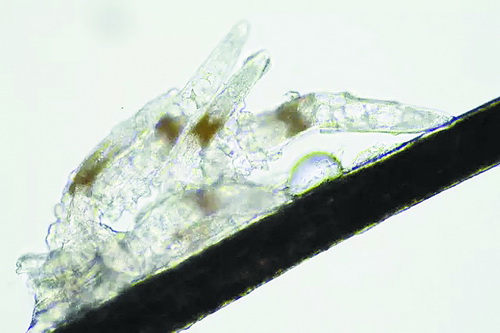

顯微鏡下長(zhǎng)在睫毛中的螨蟲

冬天來(lái)了,氣溫降低,睫毛上的“隱形殺手”蠕形螨卻沒有要冬眠的意思。廈門大學(xué)附屬?gòu)B門眼科中心11月初開設(shè)蠕蟲性瞼緣炎門診以來(lái),每天來(lái)查螨的市民都特別多,短短一個(gè)多月,已有近千人在顯微鏡下見到長(zhǎng)期寄居在自己睫毛上,朝夕相處,卻素未謀面的蠕形螨。